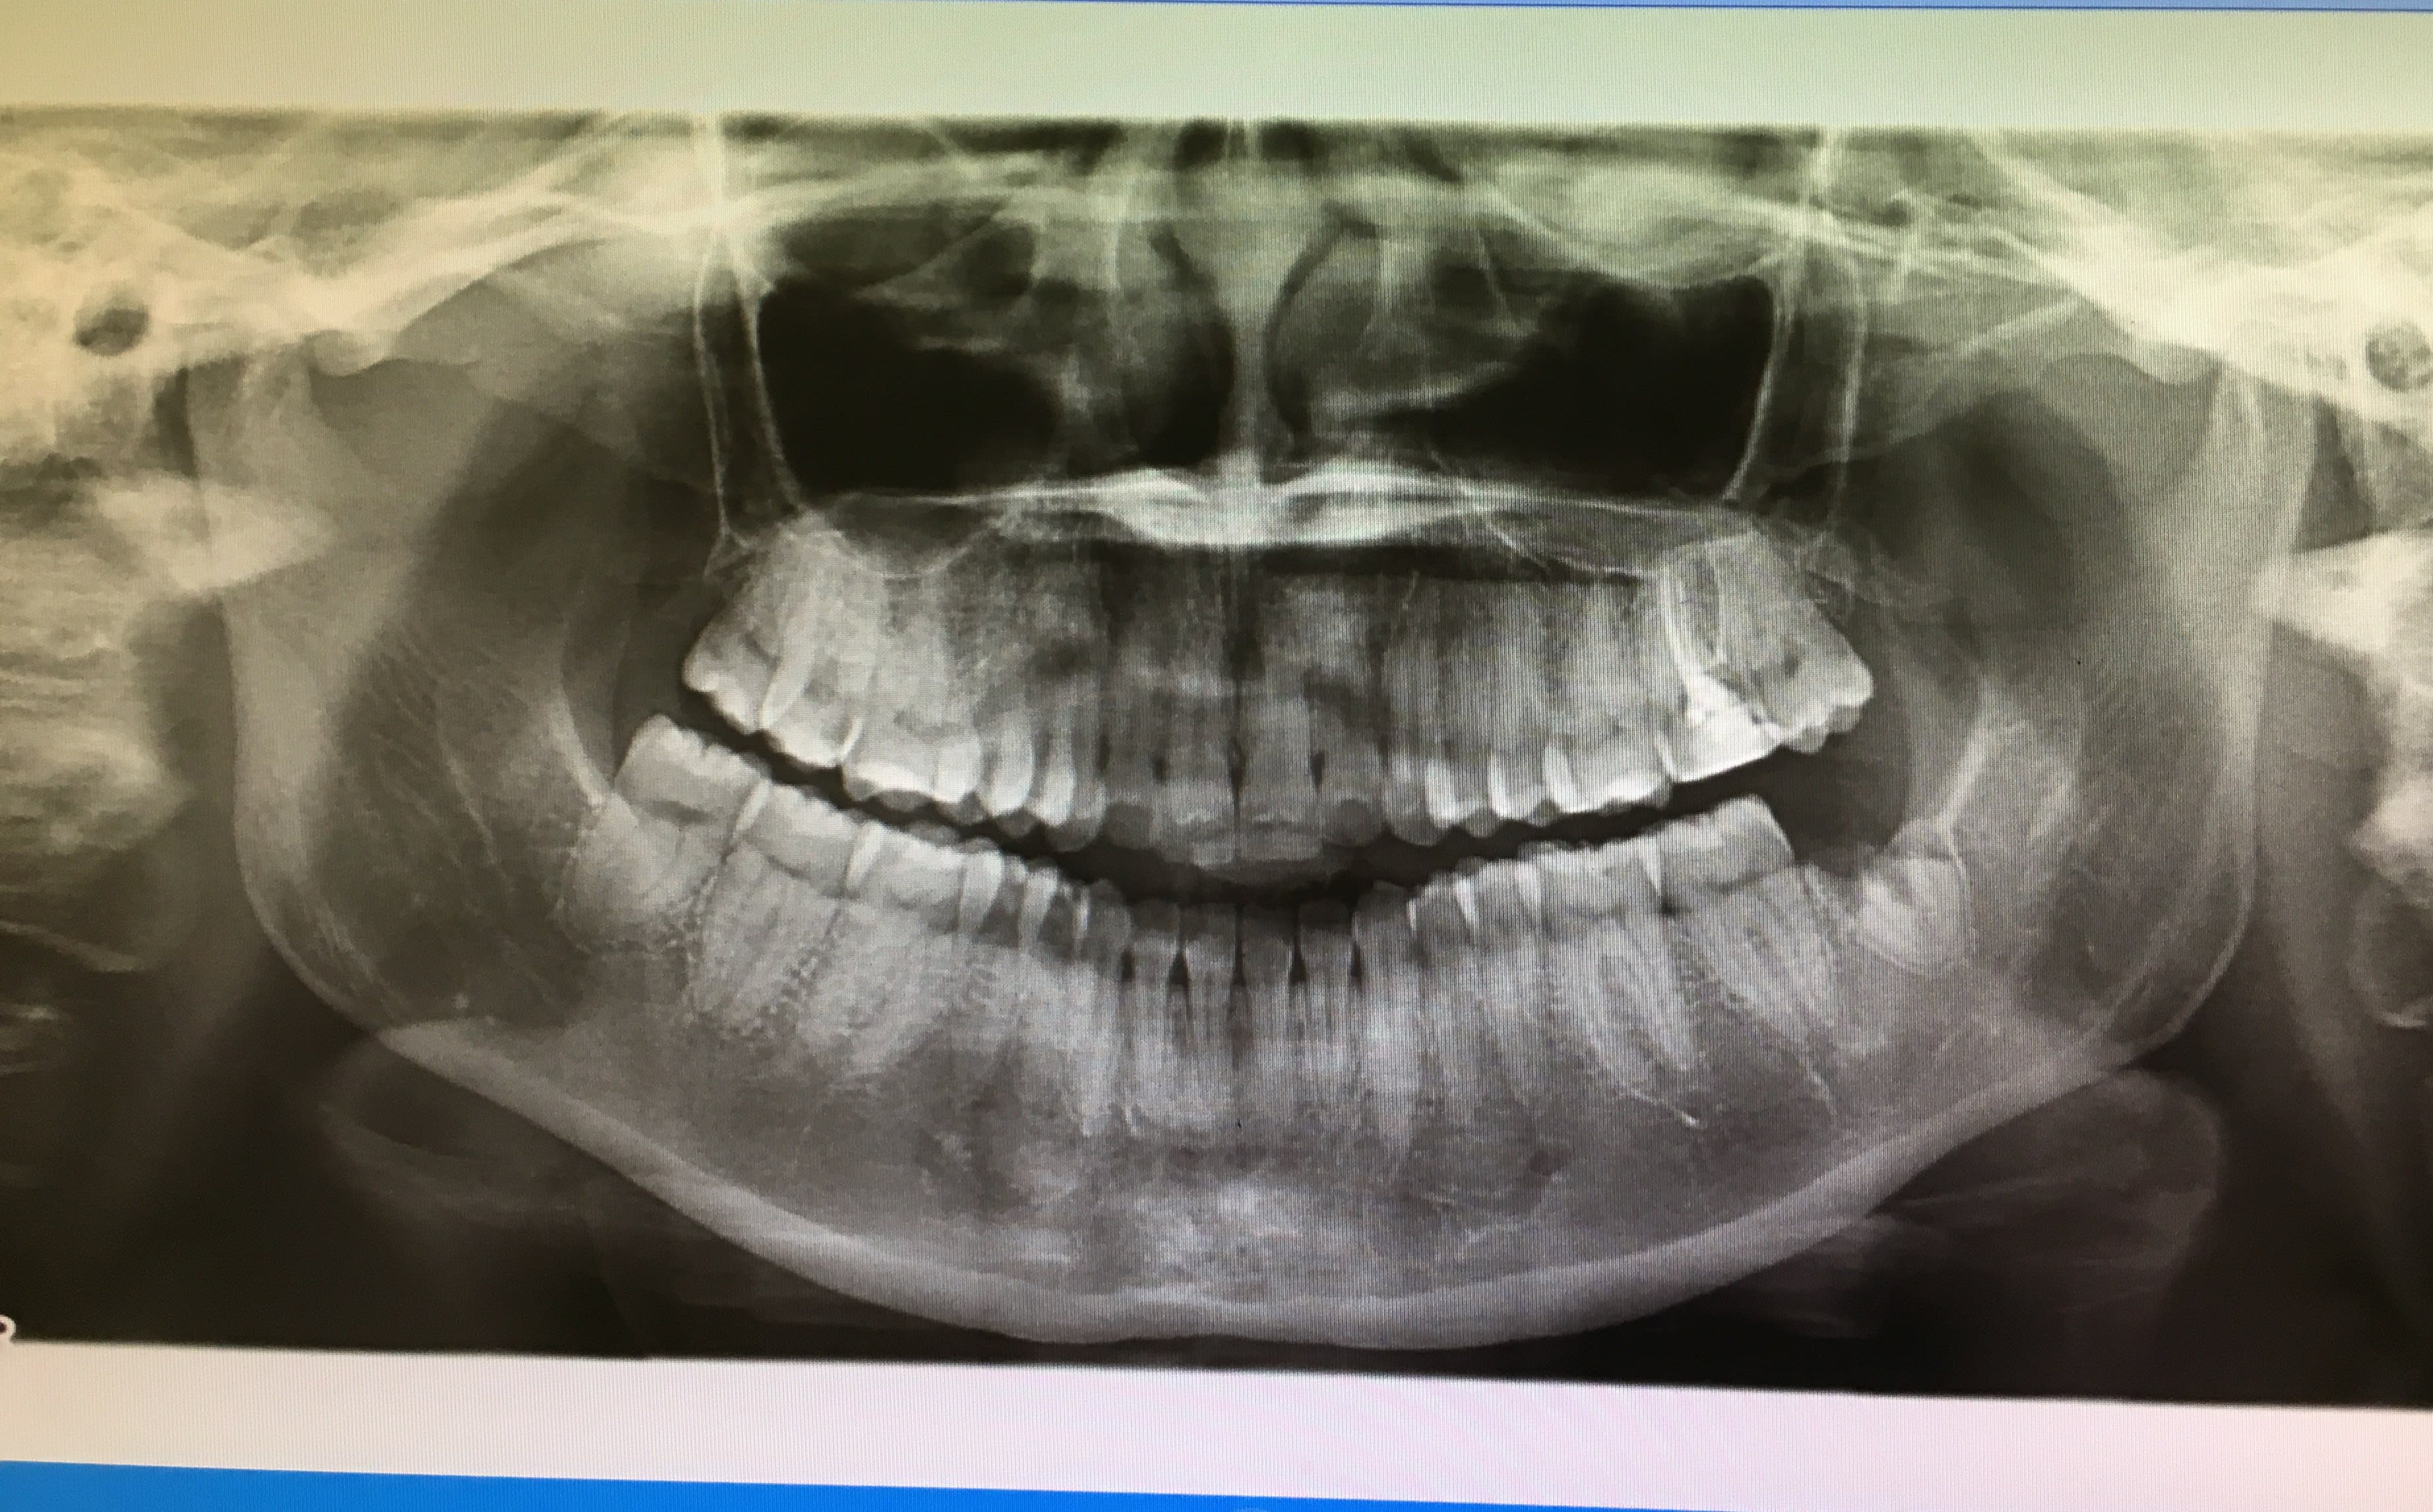

La patiente se représente le lendemain avec des d+ qui n'ont pas diminué, je décide alors d'extraire. Je réalise une pano.

>Q2: Ya t'il une façon de voir sur la premier pano que la dent n'allait pas sortir facilement. Sur la 2eme je vois que les racines sont pe joint.

- sur la pano la dent n'a pas l'air méchante mais elle est déjà bien amochée par la cavité donc cela peut vite se compliquer

Sur la pano cela semble une dent plutôt facile. Un coup d’élévateur en distal jusqu'à ce que tu dilates l'os, puis davier si nécessaire. Difficile de faire une séparation de racine vu qu'elles sont fusionnées apicalement..